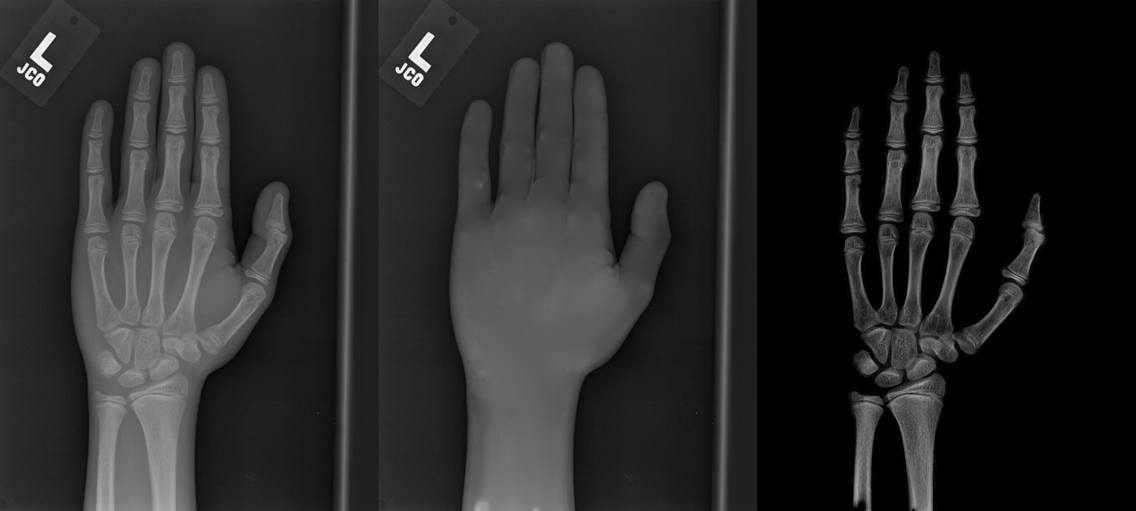

We performed three experiments for our method. First, we perform our method on several X-ray images, showing our method is not restricted by specific imaging objects. Second, we compared our method with image enhancement method and dehazing method, showing that our modification of the original dehazing indeed helps in this task. Third, we perform our method on a hand X-ray image dataset, showing its effectiveness and efficiency.

Several results from our method are shown in Fig. 7. The left column is the original input image. The right two columns are the soft tissue and bone image, respectively. It can be told that the soft tissue image is smooth as we assumed. Meanwhile, the bone image has better image contrast as desired. Moreover, our method can reach real-time performance on these X-ray images. The running time of our method on these images is reported in Table I.

In the third experiment, we applied our method on a hand X-ray image data set (RSNA), which contains more than 10,000 hand X-ray images. And the image has high resolution (usually larger than ). These images are collected from clinical applications. Therefore, we can apply our method on these practical images, showing the efficiency and effectiveness of our method on real high resolution images.

In each panel of Fig. 10, the input image (left) is decomposed into soft tissue (middle) and bone image (right) by our method. Although we only show the first ten images from the data set, the results for the rest images are similar.

The bone images have better image contrast since the parameter is theoretically guaranteed. Such enhancement can also be directly told by radiologists. Such enhancement is good for bone diagnosis in practical applications.